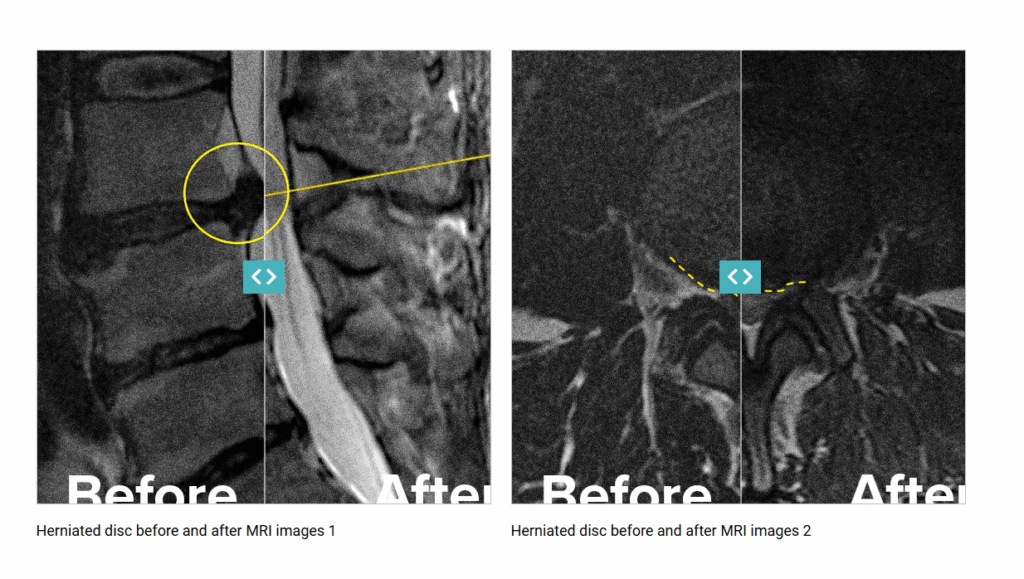

MRI Images Following The Regenexx PL-Disc Injectate for a Herniated Disc

The MRI images below show before-and-after views of an individual treated with the Regenexx PL-Disc injectate for a subligamentous disc herniation. Following the procedure, the individual reported that it helped reduce their discomfort and supported their return to regular activities within several weeks.

Scroll down to view the MRI taken before the procedure using the Regenexx PL-Disc injectate. The white or lighter area highlights the herniated disc material. Scroll to the left to view the follow-up MRI captured two years later, which shows structural changes at the treatment site.